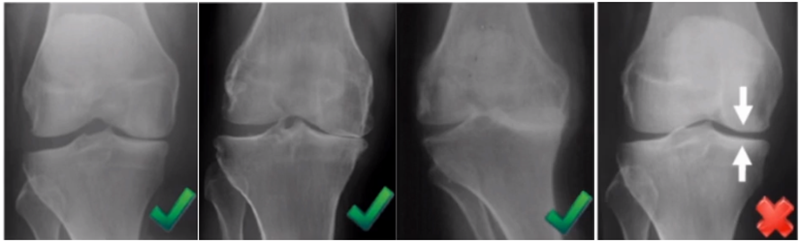

屈曲20°外翻应力:看外侧软骨

外翻应力片可以辅助评价外侧间室关节软骨厚度是否正常,以及内侧副韧带功能是否完整。外侧全层软骨、外侧有骨赘的情况下都不是禁忌证,如外侧出现软骨磨损则为禁忌证。

外翻应力片还可以观察内侧间隙,如内侧副韧带出现挛缩,间隙狭窄,那么此时不适合单髁。

检查时注意X线的投照角度要平行于关节线方向,以保证准确。

可以矫正畸形,恢复关节间隙和MCL张力